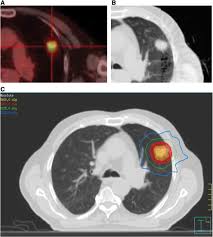

Hemoptysis Evaluation And Management American Family Physician from www.aafp.org Malignant tumors trigger inflammation in surrounding normal lung tissue, and they may obstruct your airways and interfere with normal airflow. This can lead to misdiagnosis as conditions such as irritable bowel syndrome (ibs). In this article they describe a variety of pulmonary conditions that can present with imaging features mimicking those of primary lung cancers. Pneumonia is a lung infection that leads to breathing difficulties and fluid in the lungs. When sarcoidosis affects the lungs, symptoms can mimic idiopathic pulmonary fibrosis including shortness of breath and a dry cough. Pneumonia can be mild and only require a week of treatment before you can. Pneumonia in people with lung cancer. Although slipping from emphysema to copd is usually not a drastic decline in health, early detection of lung cancer is critical for increasing your treatment options and improving your prognosis.

Risk Factors Of Lung Cancer In Chronic Obstructive Pulmonary Disease Download Scientific Diagram from www.researchgate.net Part of the dilemma for doctors is the significant overlap between copd symptoms and lung cancer symptoms. A fungal infection called valley fever, which can cause mild to severe lung problems (including holes in the lungs), is often misdiagnosed because the symptoms can resemble those of the flu or. Copd is a major risk factor for lung cancer. This, in turn, may cause collapse of the air sacs surrounding the tumor. We'll also look at some methods and medical tests commonly used. But, time is of the essence. But recent evidence suggests that copd itself is an independent risk factor for developing lung cancer, separate from any smoking history. By the time the doctor recognizes that treatment has not worked and more testing or a specialist is needed, valuable time is wasted.

Lung cancer develops due to the overgrowth of. This test can also be used to look for masses in the adrenal glands, liver, brain, and other organs that might be due to the lung cancer spread. A fungal infection called valley fever, which can cause mild to severe lung problems (including holes in the lungs), is often misdiagnosed because the symptoms can resemble those of the flu or. It can also show the size, shape, and position of any lung tumors and can help find enlarged lymph nodes that might contain cancer that has spread. Keep in mind that the symptoms of lung cancer in women. However, primary care physicians may have difficulty in classifying up to 20% of patients with obstructive pulmonary symptoms. That's because the symptoms of emphysema can easily conceal copd, and copd can conceal the presence of lung cancer. Despite the importance of all the causes mentioned by the authors, we would like to emphasize the relevance of fungal infections as an important cause of pulmonary nodules and masses that can mimic lung. That's because copd and lung cancer share common causes, including cigarette smoking and premature lung aging. Accurate diagnosis of copd is therefore critical. Furthermore, lung cancer symptoms, such as a persistent cough, back pain or weight loss, can resemble a cold or bronchitis and may not raise suspicions of lung cancer. Part of the dilemma for doctors is the significant overlap between copd symptoms and lung cancer symptoms. Other lung diseases, such as tuberculosis (tb) and chronic obstructive pulmonary disease (copd), also create a risk for lung cancer.